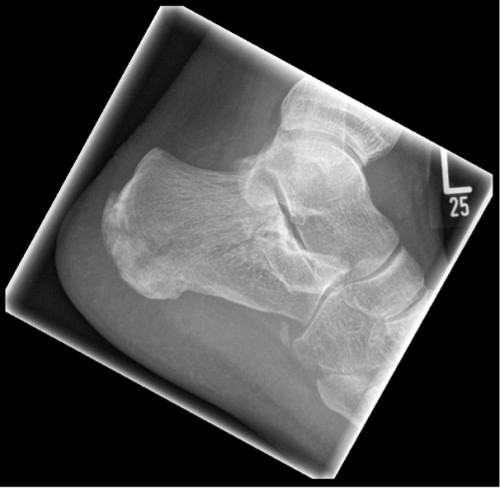

ICD: S92.0

Eine 66-jährige Patientin stellt sich in der Notfallambulanz vor und berichtet von einer Leiter gestürzt zu sein. Sie habe für ihren Enkel Lego-Spielzeug vom Dachboden holen wollen und sei dabei von der Leiter gerutscht. Sie sei auf ihren beiden Fersen gelandet und anschließend auf den Rücken gefallen. Der linke Fuß sei seitdem nicht belastbar, der rechte Fuß schon. Am rechten Fuß sei jedoch eine Schwellung im Bereich der Sprunggelenke sichtbar geworden.